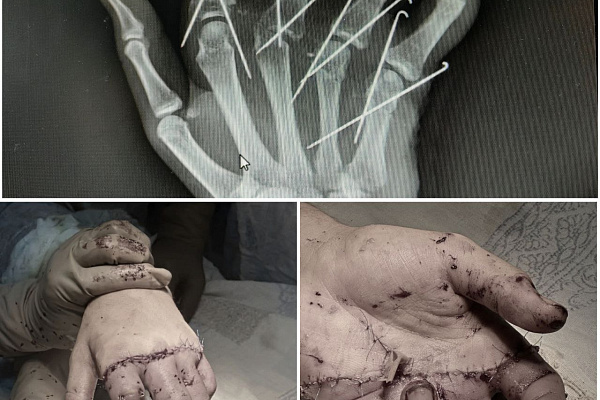

Помимо артерий и вен, Владимир Кельметр восстановил и все другие важные анатомические образования – сухожилия, нервы, мышцы; насколько возможно сопоставил повреждённые кости и зафиксировал их спицами.

После выписки он остаётся под наблюдением и еженедельно приходит на перевязки. Во время очередного посещения ему удалили фиксирующие спицы. Сейчас главная его задача – усердно выполнять упражнения на восстановление двигательной функции. При должных тренировках пальцы вновь начнут слушаться и примут более правильное положение.